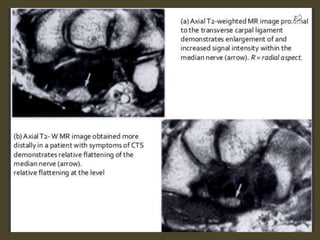

Swelling, deformity, abnormal signal of the median

nerve.